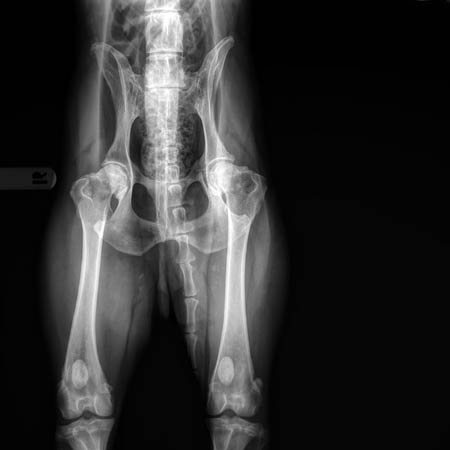

Heupen en rug Ace, 11 jaar

(04-07-2019)

| Uitleg heupfoto's: rechts een uitvergroting van de linkerheup van de linker foto (dit is de slechtste heup). In geel zijn de botwoekeringen aangegeven en de onregelmatige lijn van de heupkop. De kommen zijn diep genoeg, de rechter kop zit mooi diep, de linker iets minder diep. | |